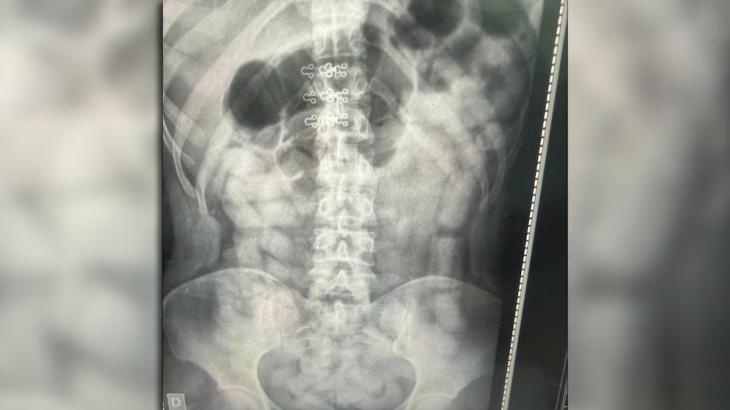

Allí, los efectivos encontraron 249 envoltorios con más de 3 kilos de cocaína entre pertenencias y prendas de tres mujeres. Sin embargo, la clave del caso apareció horas después. A partir de estudios radiográficos practicados a todos los pasajeros, se detectaron cuerpos extraños en el abdomen de seis personas, cuatro mujeres y dos hombres.

Los sospechosos fueron derivados bajo custodia a los hospitales de Santa Ana y Los Sarmientos, donde expulsaron un total de 503 cápsulas que superaron los 6 kilos de cocaína. En total, el procedimiento permitió secuestrar 752 cápsulas con un peso de 10 kilos 316 gramos, según el conteo de Criminalística.